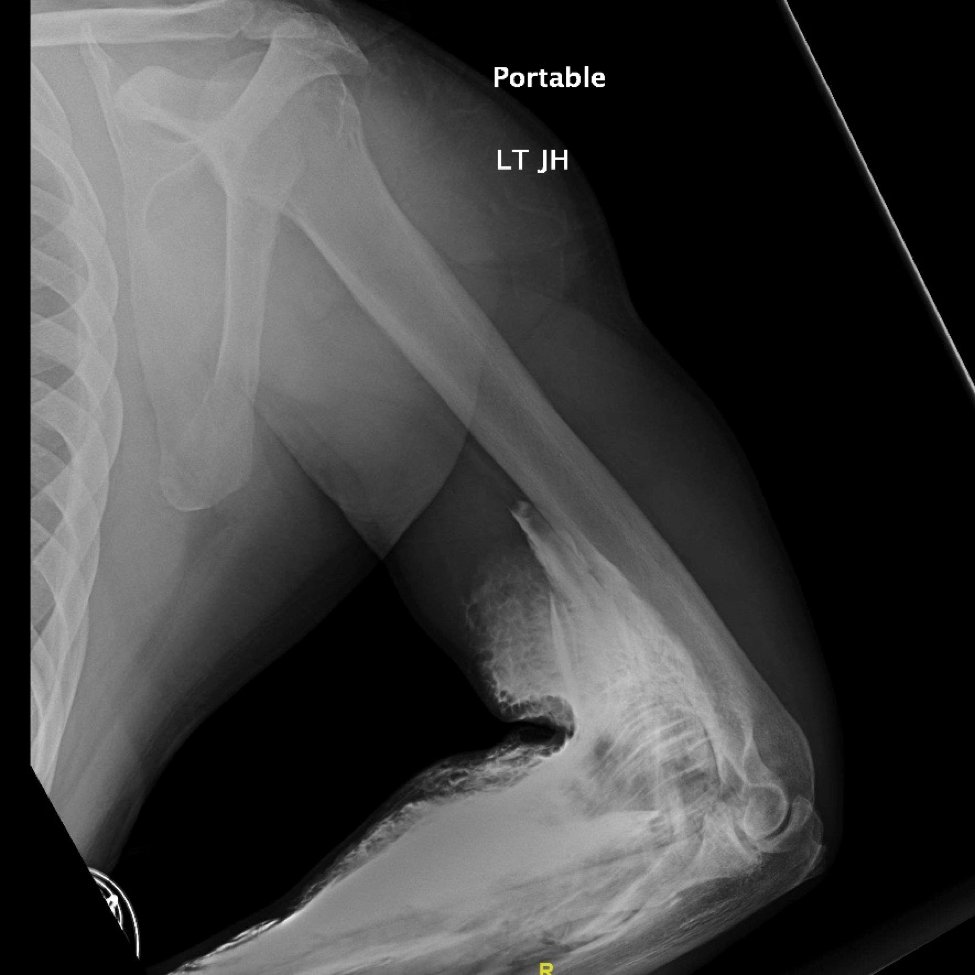

Significant findings:

The two radiographs demonstrate extravasation of radiopaque iodinated contrast in the lower left upper extremity with most seen in the left antecubital fossa and left proximal forearm. Extravasation is seen in the subcutaneous and subfascial tissue.